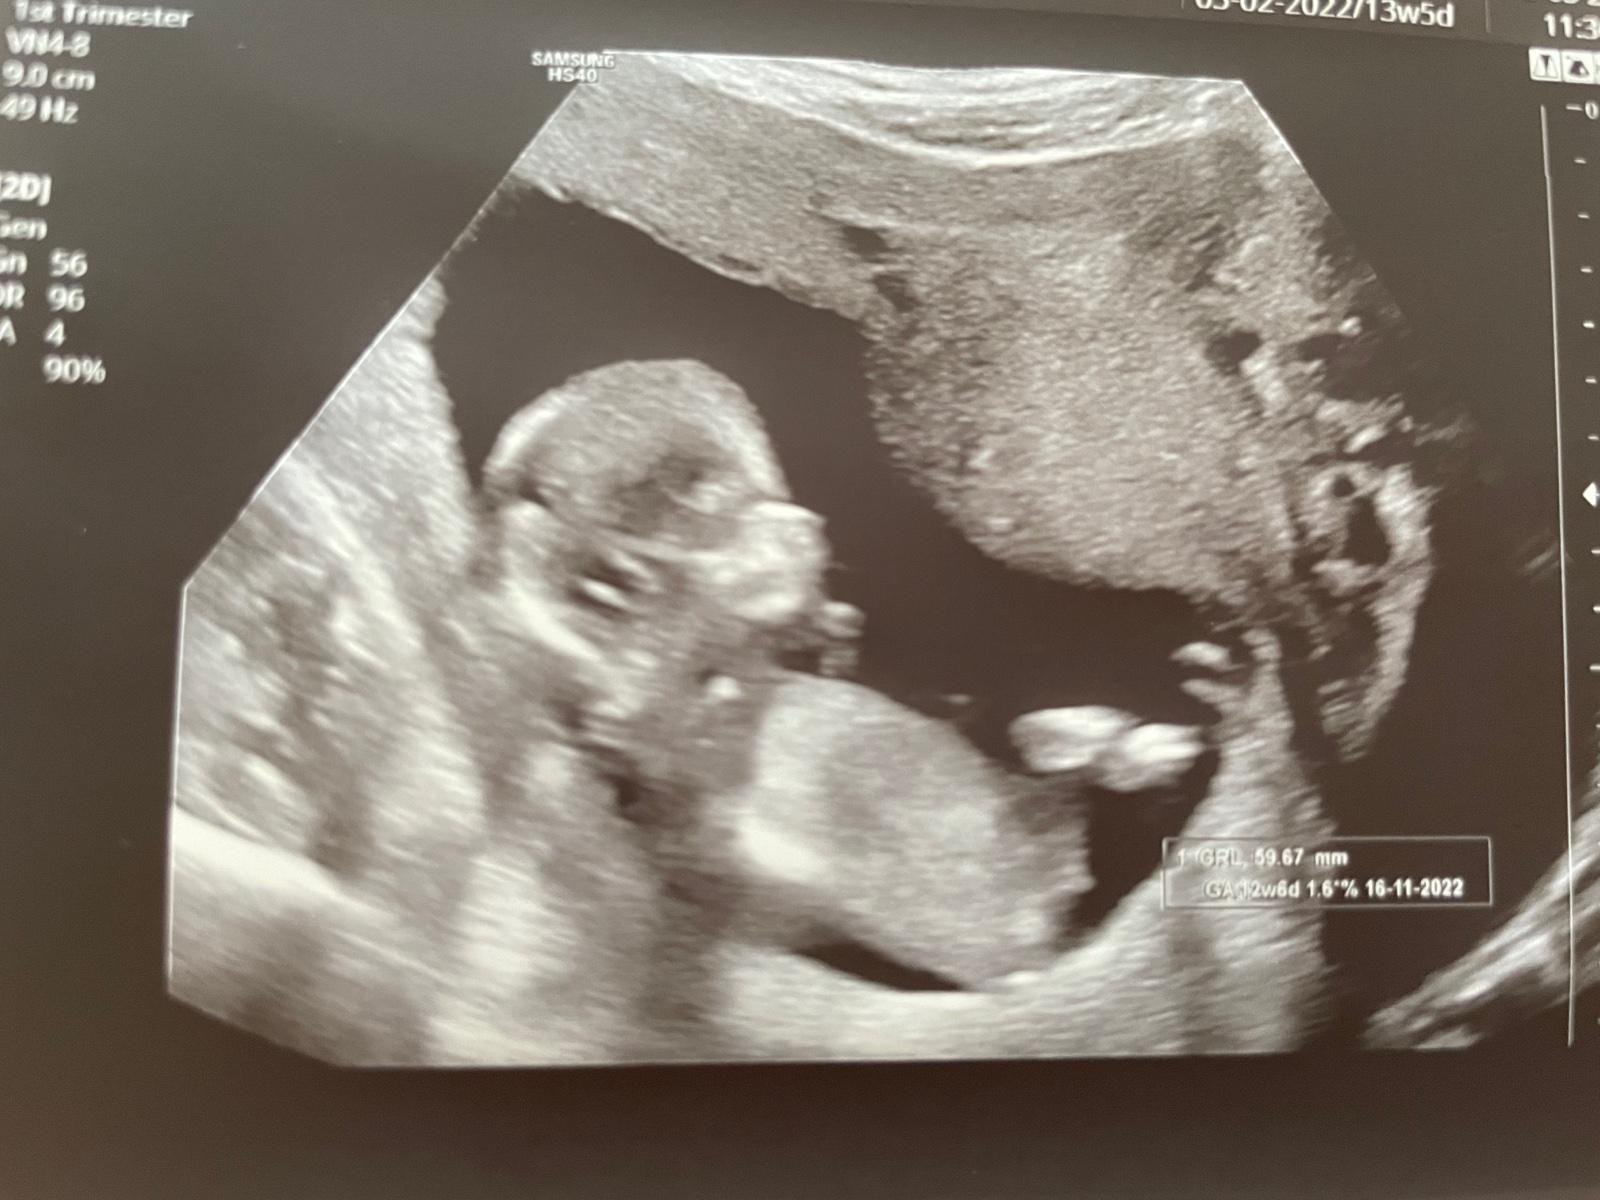

Jaké je pohlaví miminka? Podělte se o názor.

Děkuju za typy, já se taky přikláním spíš k té holčičce. Přijde mi, že tam vyloženě nic “netrčí” 🤔 Ale nevím 🙉

Ja teda vidím mimino s nohama 😀 a absolutně žádné hrboly, nic..podle me je to naprosto nepoznatelne ještě 🙂

@viki3 myslím, že holka